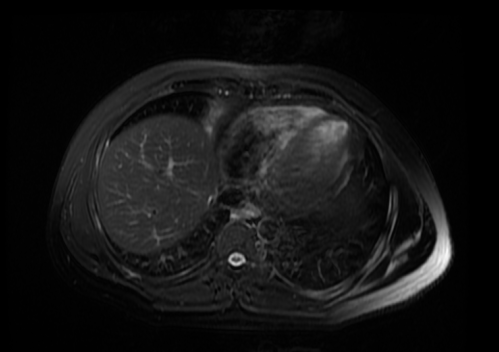

2022.05.08化疗两周期后复查肝脏MRI:肝VIII段低密度影,大小约2.3cm×1.9cm

2022.09.21肝脏放疗结束后复查肝脏MRI:肝VIII段转移灶治疗后改变,病灶基本消失。

2023.01.14定期复查肝脏MRI:肝VIII段转移灶治疗后改变,未见复发征象。

2023. 04.26复查肝脏MRI:肝VIII段转移灶治疗后改变,未见复发征象。

“医生们定期进行肝脏磁共振检查,结果显示肿瘤逐渐缩小,如同拨云见日。”邱素芳主任介绍,鼻咽癌治疗一定要边观察边调整,根据病人的实际情况和疗效来调整治疗方案及强度、在综合治疗的同时,又要具有个体化特点。

当放疗结束后程先生再进行复查时,喜讯传来——肿瘤完全缓解,已经在影像学上消失不见了,程先生一家开心不已。